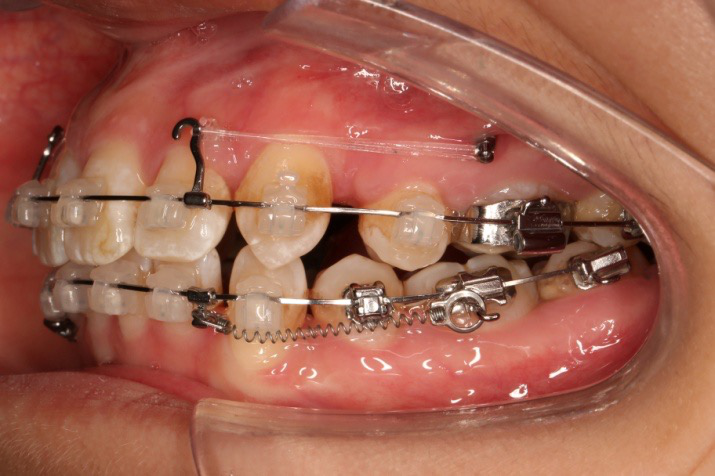

2016.10.31  初戴,0.013cu-niti2017.1.13  上颌加TPA,U56间斜形植入韩国庆北1312-08种植钉,上下0.16cu-niti

2017.02.16  上下0.014*25 cu-niti,50g 拉尖牙远中

2017.04.28

2017.04.28  上0.016*25ss 13、23近远中约5度 v形曲,下0.017*25ss

2017.05.26  磨牙近中倾斜,下颌36、46加power arm

2017.07.25

2017.07.25  上前牙加颈部弹力线